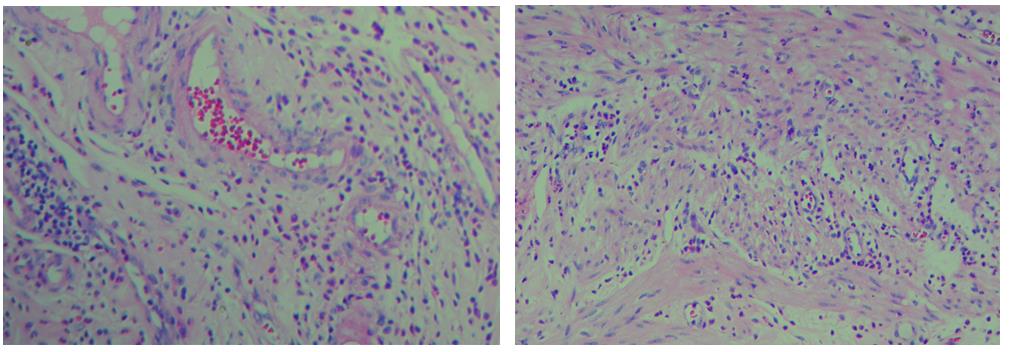

【實際染色效果】

細胞中的細胞核由帶負電荷的酸性物質組成,與帶正電荷的堿性染料蘇木素的氧化物三氧化蘇木紅有較強的親和力;而細胞漿則相反,因含有帶正電荷的堿性物質而與帶負電的酸性染料曙紅Y的親和力較強;細胞或組織切片經HE染色后,細胞核被染成藍紫色,細胞漿、紅細胞、肌纖維、膠原纖維、結締組織、嗜伊紅顆粒等被染成不同程度的紅色、粉紅色或橙紅色,與藍色的細胞核形成鮮明的對比,因此更易于觀察細胞或組織中正常成份和病變成份的一般形態結構。